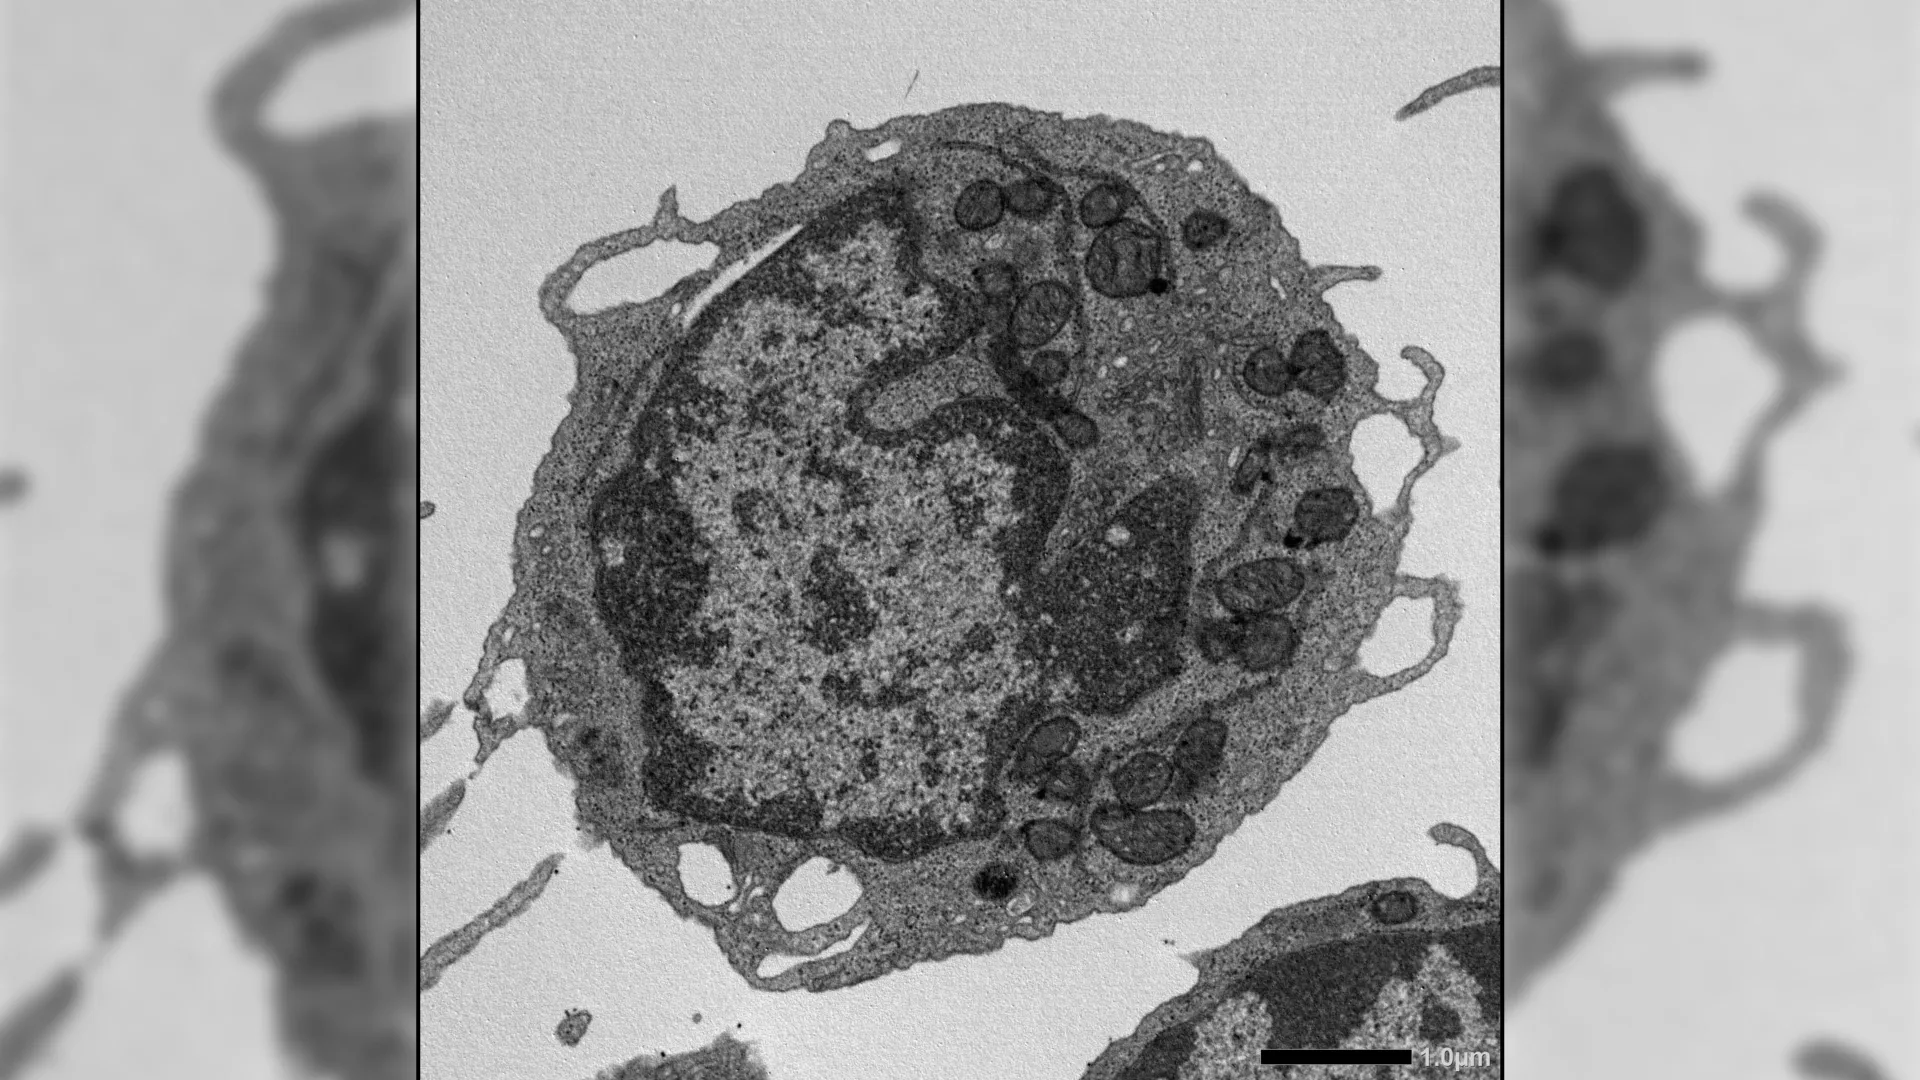

Complementing these in vivo assessments, a battery of advanced molecular and cellular techniques provided granular insights into the underlying mechanisms. These included flow cytometry for cell surface marker analysis and cell sorting, ex vivo expansion assays to assess proliferative capacity, RNA sequencing (RNA-seq) to comprehensively map gene expression profiles, assay for transposase-accessible chromatin sequencing (ATAC-seq) to probe chromatin accessibility and regulatory regions, high-resolution imaging for detailed morphological analysis, metabolic testing to evaluate cellular energy production, and detailed studies of mitochondrial function. The synergistic application of these diverse methodologies enabled the researchers to scrutinize the impact of MLKL on HSCs at multiple, interconnected levels of cellular organization and function.

Upon activation in response to cellular stress, MLKL was observed to transiently translocate to the mitochondria, the powerhouses of the cell responsible for energy generation. Within these vital organelles, MLKL instigated damage by disrupting the mitochondrial membrane potential, altering the structural integrity of the mitochondria, and consequently impairing their energy-producing capabilities. These detrimental effects on mitochondrial function were directly linked to the hallmarks of HSC aging, including a diminished capacity for self-renewal, a reduced output of lymphoid progenitor cells, and a pronounced skewing of differentiation towards the myeloid lineage.

Remarkably, these observed improvements in stem cell function occurred without substantial alterations in global gene expression patterns or chromatin accessibility. This observation strongly suggests that MLKL exerts its pro-aging effects through mechanisms that operate downstream of gene regulation, particularly at the level of cellular ultrastructure, such as the mitochondria, rather than by directly impacting DNA regulation or triggering inflammatory cascades.